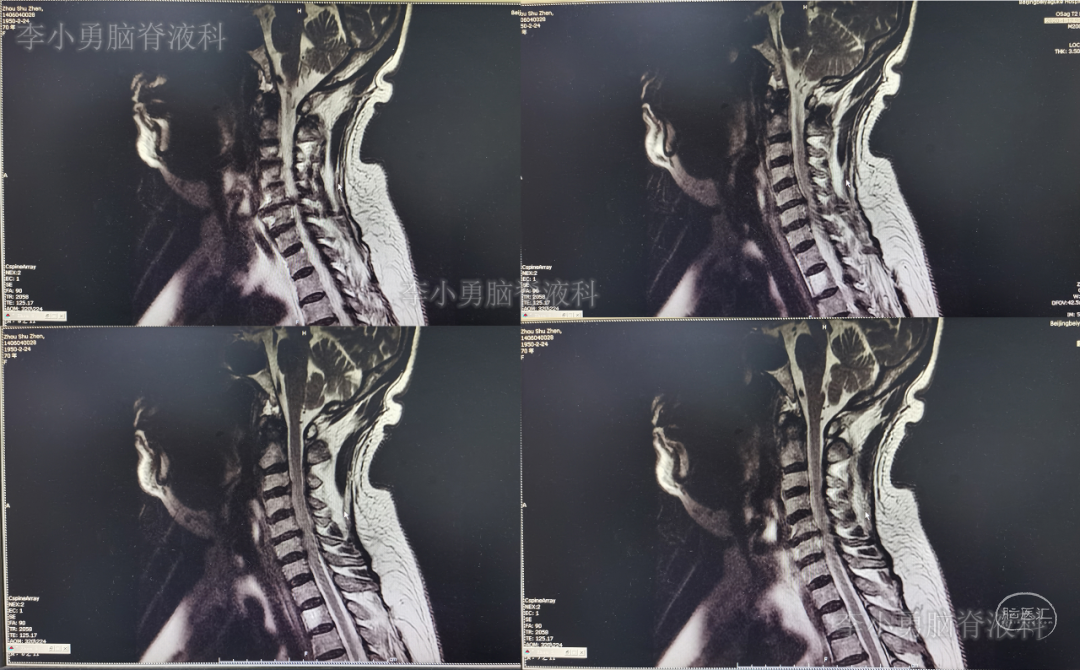

2020年8月1日(即第一次颈椎病术后第101天)患者复查颈椎MR示颈椎病,椎管狭窄,颈髓受压(图-5)。

图-5:2020年8月1日颈椎MR